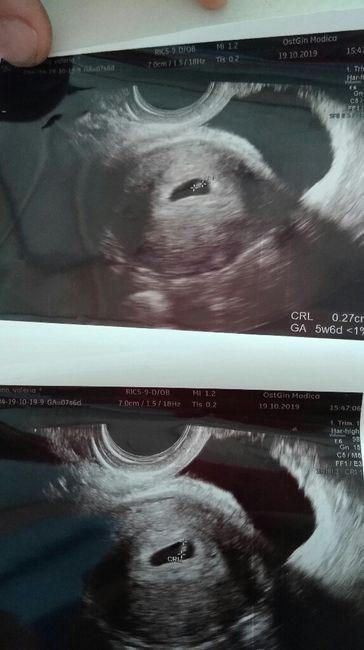

Ragazze la scorsa volta ci avevamo azzeccato e sarebbe dovuto nascere Leonardo. Questa volta invece che dite?maschio o femmina? Eco interna 6settimana

Ho caricato una foto nel post di Valeria